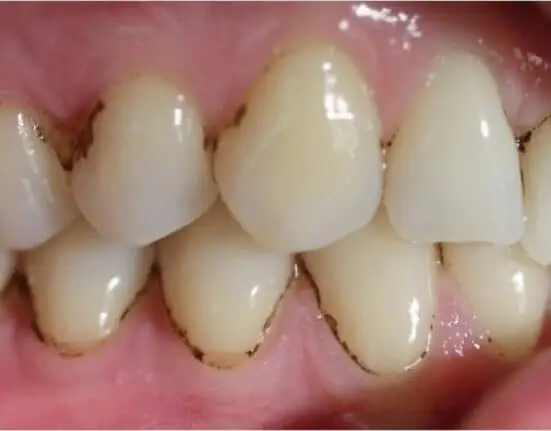

The dark pigmentations that appear around the gums on dental enamel have a bacterial origin, and currently, there is no definitive therapy to remove it entirely. Researchers with the Oral Microbiology Group of the CEU Cardenal Herrera University (UCH) of Valencia, Spain, however, have conducted the first study of the metagenomics of dental black plaque in adults who have it, in collaboration with Microomics Systems SL.

In their study, the researchers described and compared the microbial diversity of dental white plaque and the black stains that appeared on 27 adults who were receiving treatment at the CEU UCH University Dental Clinic. The characterization of the taxonomic profile of the samples and comparison of the microbiomes of white and black dental plaque had only been done on children before, the researchers said, who most often suffer from these types of stains.

With this data, the researchers have created the first map of the microbiome of dental black plaque in adults, finding that there is less variety in bacterial species in dental black plaque than in dental white plaque. The five most common bacterial species found in the dental black plaque of adults were from the Capnocytophaga, Leptorichia, Fusobacterium, Corynebacterium, and Streptococcus genuses. The study also made it possible to detect the existence of functional routes among the microbiomes of white and black dental plaque.

The routes of biosynthetic compounds of the heme group are key to the formation of dental black plaque, the researchers said, explaining the black color. The sequestration of iron by the bacteria of the black plaque and its subsequent metabolism toward biosynthetic routes of the heme group are essential for the formation of this type of plaque, the researchers said. Along with new research for its complete description, this finding will make it possible to design treatments that effectively prevent the appearance of dental black plaque, the researchers said.